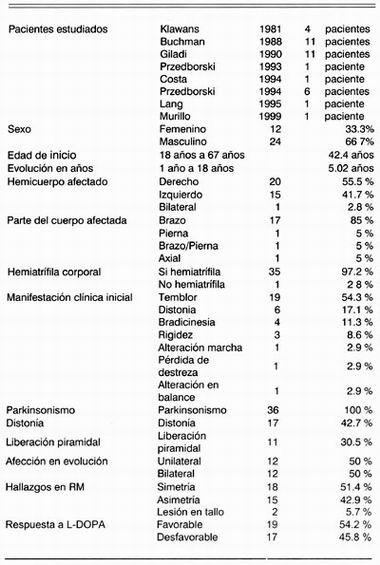

Se realizó una revisión en Medline de 1966 a 1999 de los artículos relacionados con el tema. Se encontraron sólo 10 artículos relacionados con hemi-parkinsonismo-hemiatrofía. De estos, dos son cartas al editor y uno no se pudo localizar, por lo cual se cuenta con 7 artículos en los cuales se describen características epidemiológicas de HP/HA 1,2,5-9 (cuadro 1).

Hasta la fecha tan solo se encuentra con 36 pacientes incluyendo el nuestro los cuales cumplen las características de HP-HA. De estos 12 (33.3%) son femeninos y 24 (66.7%) son masculinos. La edad de inicio de las manifestaciones clínicas son muy variadas entre 18 a 67 años con una media de 42.4 años. La duración en años de la enfermedad, al momento del diagnóstico se pudo obtener en 21 pacientes, siendo entre 1 a 18 años con una media de 5.02 años. En 20 pacientes (55.5%) las manifestaciones iniciaron en hemicuerpo derecho, en 15 (41.7%) en hemicuerpo izquierdo y en 1 paciente (2.8%) de manera bilateral. La parte del cuerpo afectada al inicio de la enfermedad, se obtuvo de 20 pacientes, de los cuales 17 pacientes (85%) iniciaron en brazo, 1 paciente (5%) en pierna, 1 paciente (5%) en brazo y pierna y 1 paciente (5%) presento afección axial. La hemiatrofia se detecto en 35 (97.2%) de los casos, y en uno (2.8%) no se pudo confirmar. La manifestación clínica inicial fue temblor en 19 pacientes (54.3%), bradicinesia en 4 pacientes (11.3%), distonía en 6 pacientes (17.1 %), alteraciones en la marcha en 1 paciente (2.9%), pérdida de la destreza de movimientos finos en 1 paciente (2.9%), rigidez en 3 pacientes (8.5%) y alteraciones en el balance en 1 paciente (2.9%). Durante la evolución completa de los pacientes, se detecto parkinsonismo en 36 pacientes (100%) y distonía solo en 17 pacientes (42.7%) mientras que 19 pacientes (57.3%) permanecieron sin distonía. Los datos de liberación piramidal se encontraron en 11 pacientes (30.5%) durante la evolución de la enfermedad. En 24 pacientes (66.6%) se pudo documentar la afección unilateral o bilateral del padecimiento, encontrando que 12 pacientes (50%) presentaron afección unilateral y 12 pacientes (50%) presentaron afección bilateral durante la evolución de la enfermedad. En lo que respecta a IRM, se recabaron los datos de 35 pacientes (97.2%) de los cuales solo 15 pacientes (42.9%) presentaron asimetría ya sea cortical, subcortical, a nivel ventricular o en núcleos de la base, en 18 pacientes (51.4%) no fue posible demostrar asimetría alguna en IRM, y 2 pacientes (5.7%) presentaron lesiones hiperintensas a nivel de mesencefalo. Las asimetrías y lesiones mesencefálicas correlacionaron con el cuadro clínico de los pacientes encontrándose todas contra laterales al hemicuerpo con mayor afectación. Por último, la respuesta al tratamiento con LDOPA fue buena en 13 pacientes (37.1%) y moderada en 6 pacientes (17.1%). Esto da un total de respuesta favorable al tratamiento con L-DOPA en 19 pacientes (54.2%) mientras que 17 pacientes (45.8%) tuvieron mala o no tuvieron respuesta alguna al tratamiento con L-DOPA.

Podemos concluir que el síndrome de Hemipar-kinsonismo-hemiatrofia es una entidad rara que afecta principalmente a hombres (66.5%) en una edad media de 42.4 años. La duración al momento del diagnóstico es de 5.02 años. Inicia principalmente en hemicuerpo derecho (55.5%) con afección braquial (85%). La hemiatrofia corporal se documenta en el 97.2% de los casos y se manifiesta clínicamente con temblor en reposo (54.3%). Solo el 57.3% de los pacientes presentan distonía durante la evolución del padecimiento y la afección piramidal se presenta en el 30.5%. La evolución unilateral se presenta en 50% y bilateral en 50% de los casos durante la evolución del padecimiento. La asimetría en RM se documenta en el 42.9% de los pacientes y la respuesta a tratamiento se considera buena en 37.1%, moderada en 17.1% y mala respuesta en 45.8% de los pacientes.